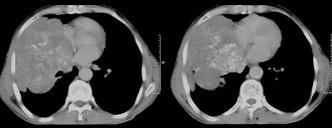

问题 50岁,男性,右侧胸痛、咳嗽、咯血3个月,请结合图像选择最可能的诊断 ( )

选项 A.纵隔肿瘤 B.肺结核 C.肺癌 D.胸膜间皮瘤 E.韦格肉芽肿

答案 C